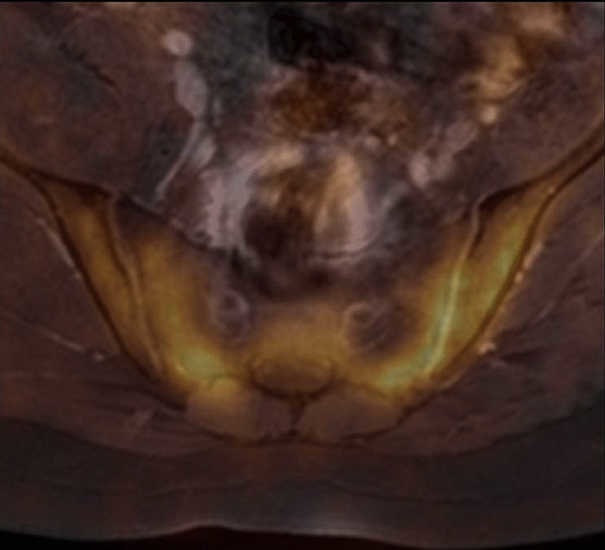

Figura 1. Tomografía computada por emisi??n de positrones con 18-fluorodesoxiglucosa (18FDG-PET) fusionada con resonancia magn??tica (RM) en corte axial de columna lumbosacra muestra una marcada avidez de la articulaci??n sacroil??aca por el radiotrazador.

Figura 2. Fusión de una imagen del gato de Cheshire con la 18FDG-PET/RM.